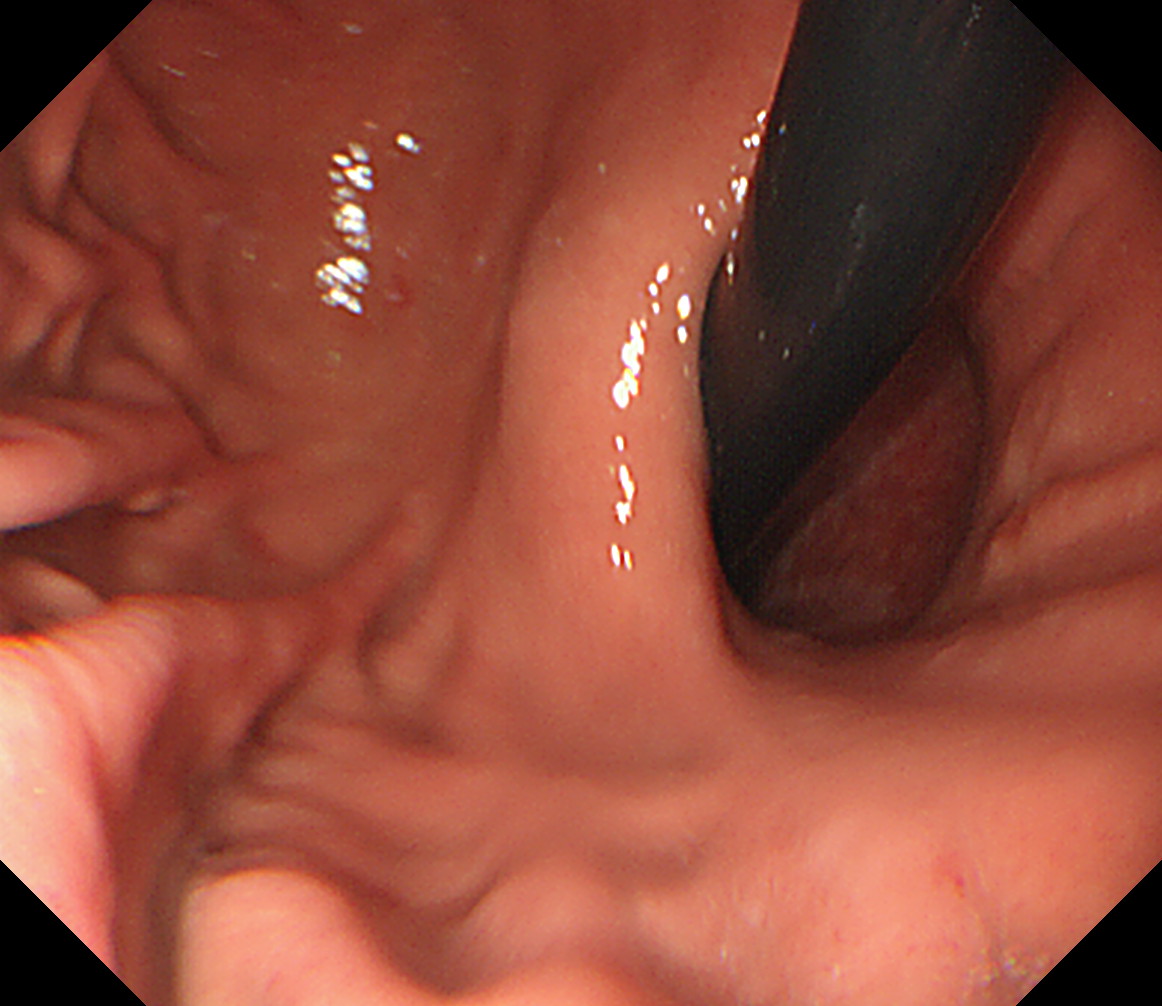

3 EGJ この人はLos-Angeles分類 GradeDの逆流性食道炎があります。 EGJ